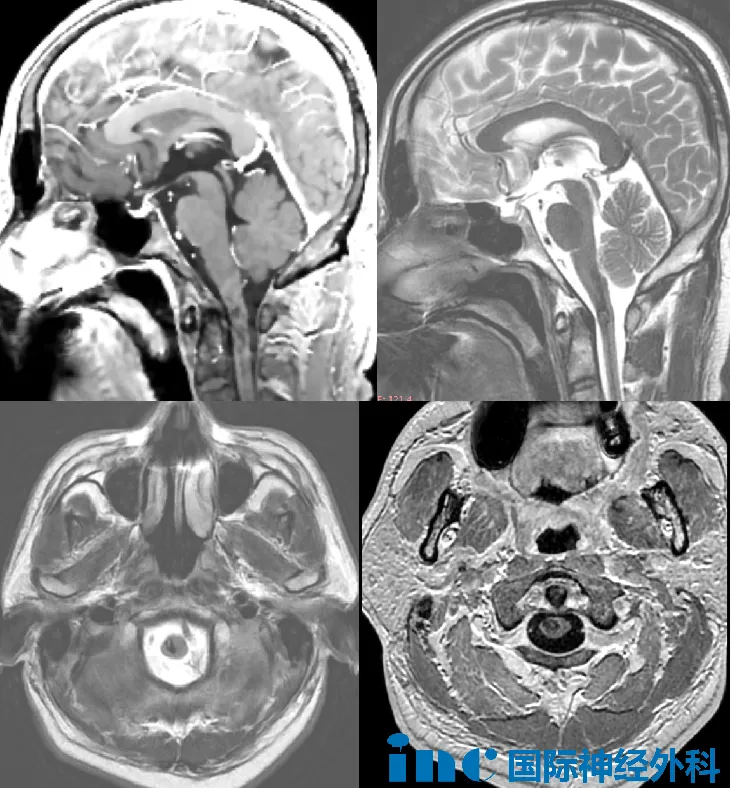

转至康复中心后,郑先生开始长期治疗,针灸、按摩、中药、小针刀等传统疗法相继应用。12月底MRI检查确诊为延髓区海绵状血管瘤,因病变紧贴生命中枢,多家医院建议保守治疗。

转机出现在病友群分享的INC巴特朗菲教授来华消息。教授分析影像后指出:"C1颈髓内海绵状血管畸形导致内生性出血并延伸至延髓下部,手术切除技术可行。虽非急诊手术,但为预防再出血应尽早干预。"他同时说明此前出血已造成神经损伤,术后症状可能改善但不完全消失。